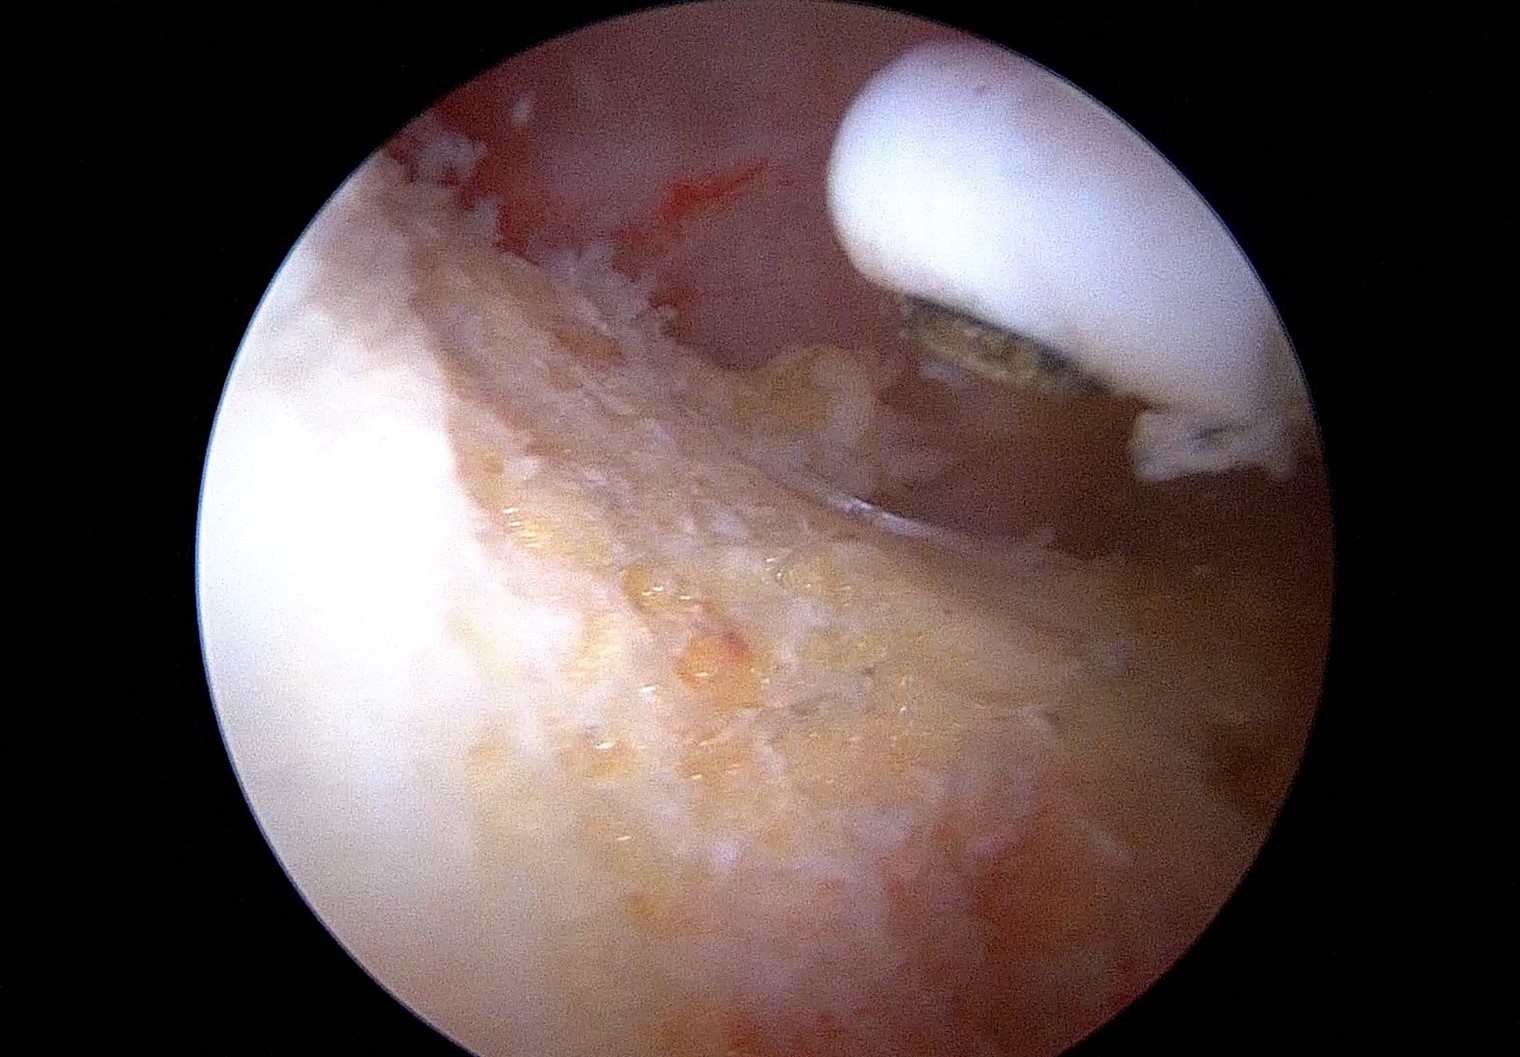

Η γωνία άλφα αποτελεί ένα ποσοτικό χαρακτηριστικό της μηροκοτυλιαίας πρόσκρουσης τύπου cam, σε περιπτώσεις ασθενών με χρόνιο πόνο στο ισχίο. Ωστόσο, τα όρια της γωνίας αυτής αποτελούν ακόμα ένα...